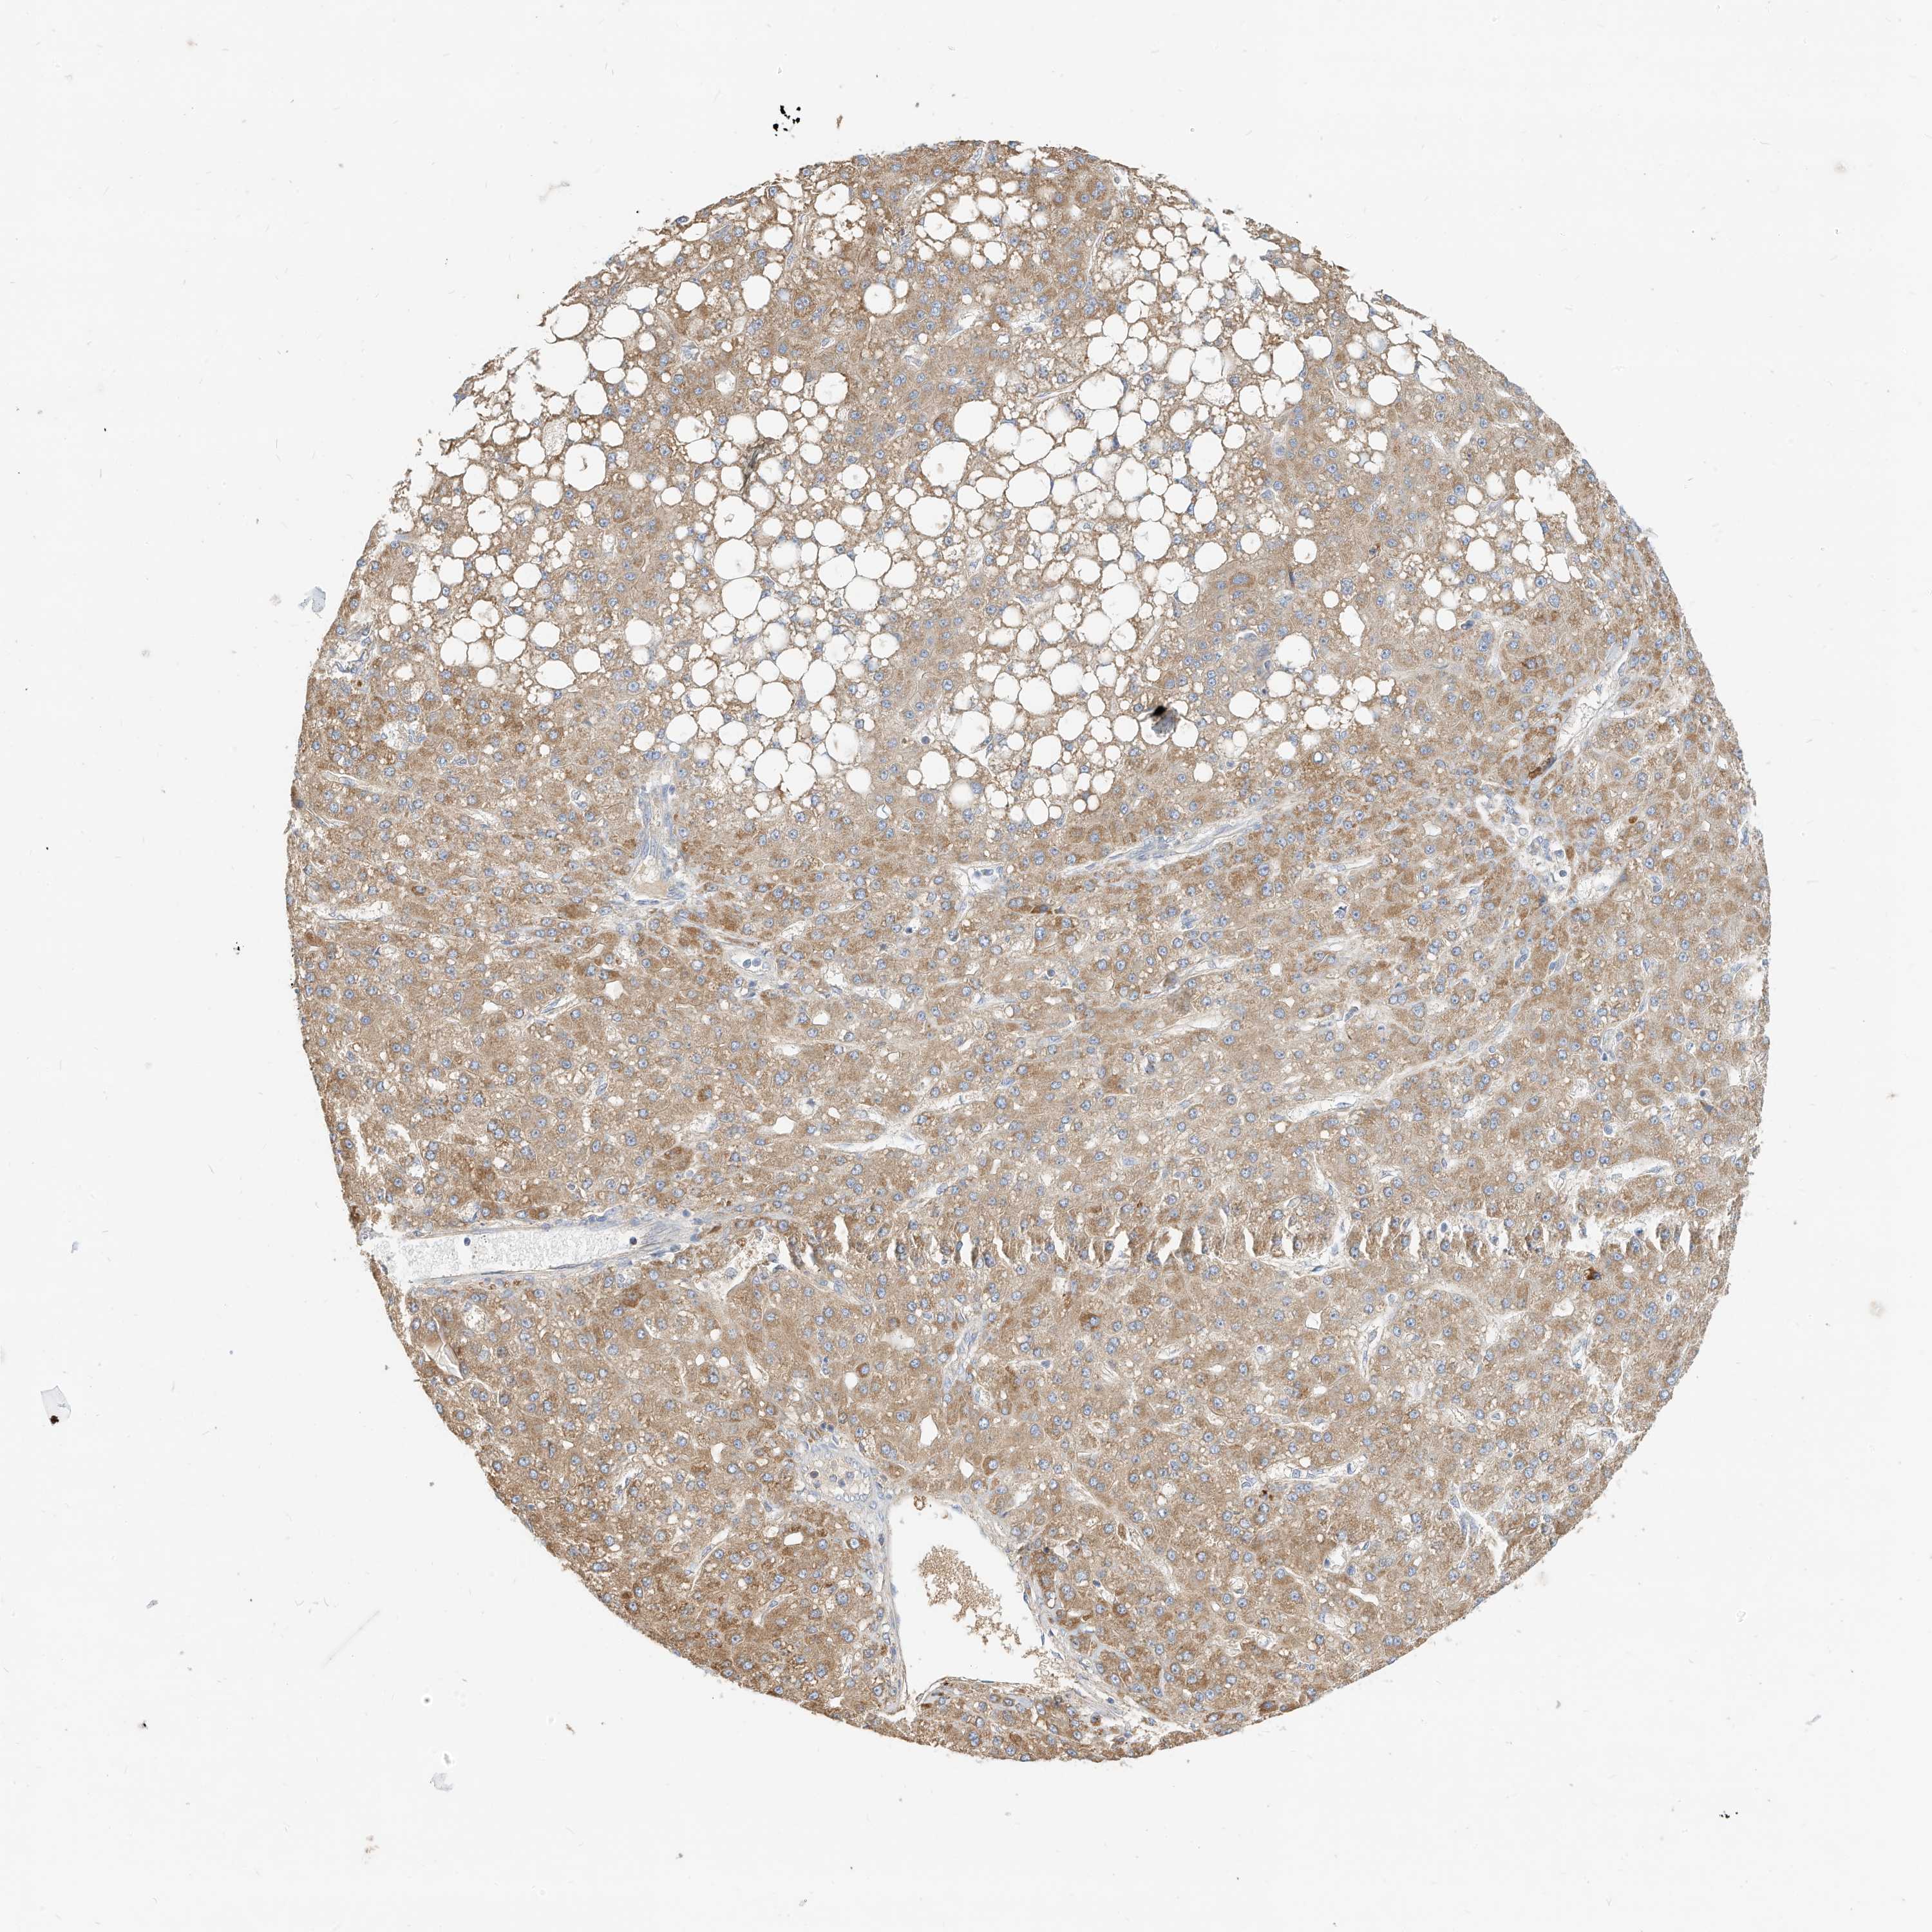

LIVER CANCER - Protein expressioni

A mouse-over function shows sample information and annotation data. Click on an image to view it in a full screen mode. Samples can be filtered based on level of antibody staining by selecting one or several of the following categories: high, medium, low and not detected. The assay and annotation is described here.

Note that samples used for immunohistochemistry by the Human Protein Atlas do not correspond to samples in the TCGA dataset.

Antibody stainingi

Antibody staining in the annotated cell types in the current human tissue is reported as not detected, low, medium, or high, based on conventional immunohistochemistry profiling in selected tissues. This score is based on the combination of the staining intensity and fraction of stained cells.

Each image is clickable and will lead to virtual microscopy that enables deeper exploration of all samples and also displays staining intensity scores, fraction scores and subcellular localization as well as patient and tissue information for each sample.

Antibody HPA030345

Staining

High

Medium

Low

Not detected

Intensity

Strong

Moderate

Weak

Negative

Quantity

>75%

75%-25%

<25%

None

Location

Nuclear

Cytoplasmic/membranous

Cytoplasmic/membranous,nuclear

Carcinoma, Hepatocellular, NOS